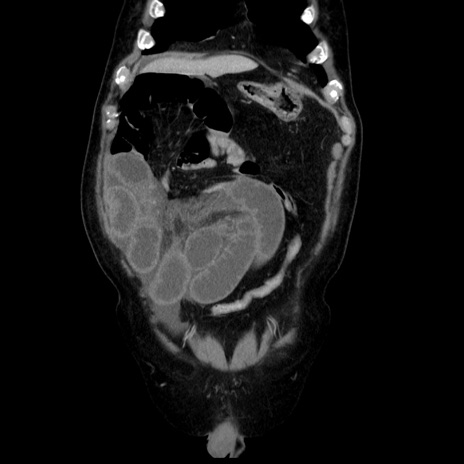

症例30(冠状断像)

【症例】80歳代男性

【主訴】臍周囲痛

【現病歴】約6時間前から臍下部痛が出現。次第に腹部膨隆・背部痛も生じてきたため来院。背部痛の場所は変化しない。

【既往歴】腎盂腎炎

【身体所見】意識清明、BT 36.3℃、BP  131/87mmHg、P 87bpm、SpO2 100%(RA)、臍周囲自発痛・圧痛あり、反跳痛なし、自発痛部位に一致して板状硬あり、腹部膨隆、腸雑音減弱、CVA tenderness両側陰性。

【データ】WBC 19600、CRP 0.33